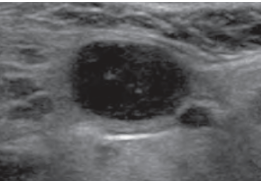

Normal lymph node US appearance

• < 1cm AP diameter

• Shape: oval (long axis), C-shaped (short-axis)

• Hypoechoic cortex

• Hyperechoic fatty hilum

• Uniform vascular hilum